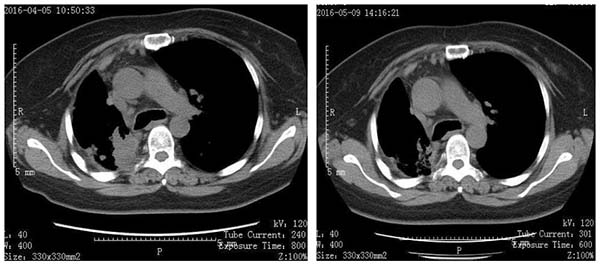

我清晰地记得,十六线治疗一个月后,鲍女士肺内病灶明显缩小,达到部分缓解(PR)状态 。那一刻,鲍女士和医生们都激动不已,这是他们共同努力的成果,是生命顽强抗争的胜利。

有图有真相

↑患者十六线治疗一月后PR,肺内病灶明显缩小